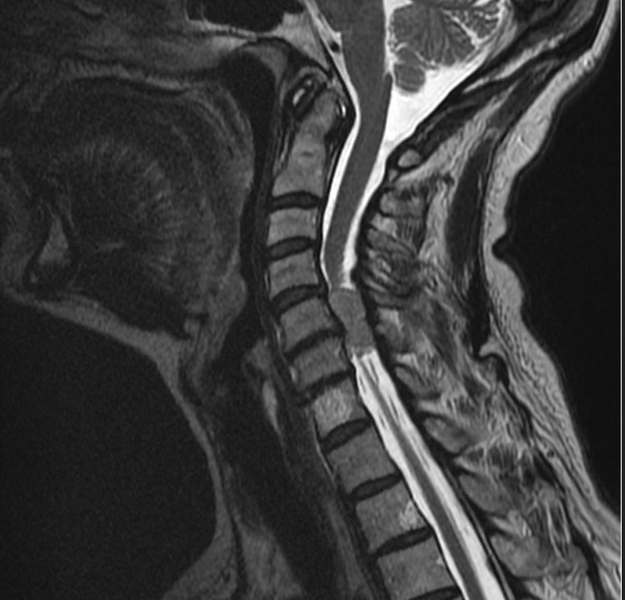

– Это немного разные вещи. МРТ шейного отдела позвоночника – узконаправленное обследование. При выполнении данной процедуры видны только позвоночник и спинной мозг. МРТ мягких тканей шеи – обследование более расширенное. При его проведении просматриваются и оцениваются мышцы, слюнные железы (подъязычная, нижнечелюстная, околоушная), щитовидная железа, пищевод, гортань, а также межфасциальные пространства. Просматривается также корень языка, грушевидные синусы, лимфоузлы, парафарингеальные (окологлоточные) области. Позвоночник и спинной мозг на МРТ шеи тоже видны, но не так детально, как на МРТ шейного отдела позвоночника.

МРТ шейного отдела позвоночника сегодня назначается больным довольно часто. Однако далеко не все пациенты понимают, для чего это делается и что процедура даст для постановки правильного диагноза. Выполнение МРТ шейного отдела позвоночника позволяет визуализировать хрящевые структуры, кости, нервные волокна, связки и мягкие ткани. Благодаря большому количеству снимков, врач может детально изучить любую из перечисленных структур и безошибочно выявить малейшие отклонения от нормы. В некоторые случаях для более четкого изображения, прибегают к использованию контрастирующего вещества. Наиболее часто это делается для оценки состояния нервных структур и сосудов.

В результате сканирования врач получает большое количество снимков среза шеи на различных уровнях и в разных проекциях. В отличие от КТ, МРТ позволяет получить четкие изображения не только костей и суставов, но и всех мягкотканых структур. Так, специалист может безошибочно определить наличие опухоли в области шеи либо выявить различные повреждения тканей.

Здоровая шея имеет на снимках позвонки без шероховатостей и дефектов, диски между ними одинаковой высоты и ширины. Структуры шеи при этом расположены симметрично, без каких-либо смещений. Также снимок дает четкое изображение костного мозга, по которому врач может легко оценить структуру его тканей. Нервные волокна свободно выходят из просвета позвоночного столба и не пережимаются какими-либо структурами. На серии снимков не должно быть признаков воспалительного процесса структур шеи, дефектов либо опухолевидных образований.

В ходе МР-исследования получают послойные изображения структур шейного отдела позвоночника в трех взаимно перпендикулярных плоскостях — сагиттальной, аксиальной и коронарной, благодаря чему радиолог имеет возможность детально рассмотреть зону интереса.

МР-томограммы шейного отдела позвоночника в аксиальной и сагиттальной проекциях

На снимках магниторезонансной томографии видны:

- позвонки;

- фиброзно-хрящевые диски;

- спинной мозг и его оболочки;

- нервные корешки;

- фасеточные суставы и межпозвонковые отверстия;

- мышцы;

- связки;

- сухожилия;

- лимфатические узлы (патологически трансформированные);

- кровеносные сосуды (при контрастировании);

- шейный отдел пищевода;

- гортань, верхние хрящевые полукольца трахеи;

- щитовидная и паращитовидные железы.

В норме шейные позвонки ровные, без шероховатостей и дефектов, расположены на одинаковом расстоянии друг от друга. Нервные корешки свободны, спинной мозг имеет прямые контуры и находится в центре позвоночного канала. На томограммах нет признаков новообразований и воспалительных процессов.

При протрузиях и грыжах на изображениях можно обнаружить выпячивание дисков, сужение межпозвоночных щелей.